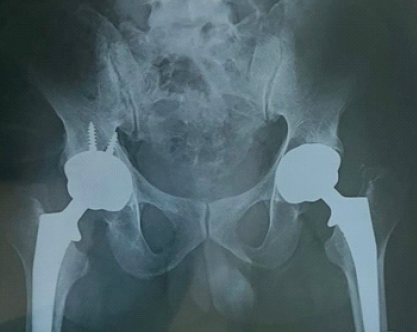

An uncemented distally loading long femoral stem with an uncemented acetabular cup was inserted and firmly fixed. The right hip was operated on subsequently with similar implants, just that the acetabular cup on the right side was fixed with two screws. Post-operative radiograph showed acceptable implant positioning (Fig. 6).

Figure 6: Post-operative radiograph.

The post-operative course was uneventful. Hip and knee range of motion exercises were started from the day of surgery, along with protected weight bearing with a walker from post-operative day 1. The patient was discharged on the 7th post-operative day and was advised walker-assisted protected weight-bearing walking for 7 weeks, after which he started walking full-weight bearing with comfort using a tripod stick initially for the first few weeks. Staircase climbing was started in 2 weeks. By the end of 2 months, the patient walked comfortably without any support and started performing his activities of daily living independently. At 4 months follow-up (Fig. 7), the Harris Hip Score was calculated to be 86, which was considered to be excellent, 100 being the highest score [2].

Figure 7: Four-month follow-up.

Femoral neck fractures in young patients are usually a result of high-impact traumatic events, and these fractures are typically unilateral – except in the case of pre-existing medical conditions such as osteoporosis, renal osteodystrophy, or hypocalcemic convulsions with epileptic attacks – wherein bilateral involvement may be seen after low-energy trauma [1]. In this case report, we show a similar case of a 40-year-old male with deranged blood parameters, pointing toward a metabolic bone disorder, who sustained bilateral femoral neck fractures following a trivial fall at home. Blomfeldt et al., in 2011, performed a large randomized controlled trial and compared the results of primary internal fixation and THA following femoral neck fractures – the authors noted that primary THA provides better outcomes over internal fixation in displaced femoral neck fractures [3]. Ben and Gordon compared the results of THA and bipolar hemiarthroplasty, and still found THA to have superior outcomes [4]. Furthermore, bilateral THA done in a single sitting, and not staged, in patients who are fit for surgery, yields better functional outcomes with an opportunity to offer early out-of-bed mobilization to the patient [5], since our patient was a 40-year-old male with no major comorbidities and was fit for surgery, who decided to proceed with bilateral THA in the same sitting. The DAA to the hip is unique, with its internervous and intermuscular plane between the sartorius and TFL, the advantages being shorter hospital stay [6], earlier functional recovery [7], and lower dislocation risks [8]. Some disadvantages are also associated with it, such as risk of injury to the lateral femoral cutaneous nerve [9], periprosthetic fractures [10], and a long learning curve [11,12]. In a review article by Ming Ang et al. in 2023, the DAA was proven to be a better approach as compared to the posterior or lateral approach, subject to surgeon experience and training [13]. Hence, we went forward with the DAA in our case. Since no muscles are actually cut, but only split in the DAA, we could mobilize the patient immediately from the next post-operative day, which helped avoid a lot of complications associated with a patient being bedridden for a prolonged period after a bilateral hip procedure. Due to this, the patient was able to walk without support and perform his activities of daily living within 2 months. The Harris Hip Score is a 100-point system that assesses pain, function, range of motion, and deformity, with a higher score indicating a better outcome [2]. At 4 months follow-up, the Harris Hip Score in our case was 86, which was categorized as excellent.